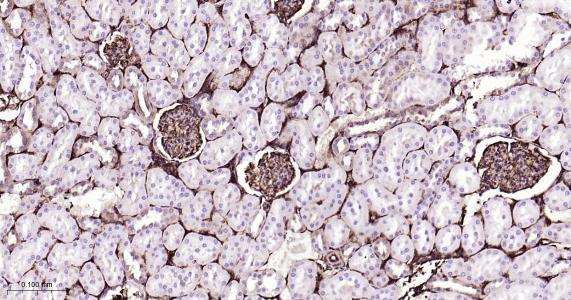

Paraformaldehyde-fixed, paraffin embedded Mouse Kidney; Antigen retrieval by boiling in sodium citrate buffer (pH6.0) for 15 min; Antibody incubation with CRMP2 Monoclonal Antibody, Unconjugated(bsm-61800R) at 1:200 overnight at 4°C, followed by conjugation to the bs-0295G-HRP and DAB (C-0010) staining.